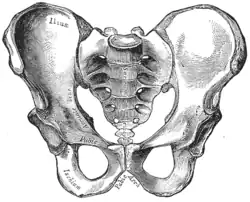

Hueso sacro en el medio, vista frontal. | ||

Imagen de la pelvis femenina, vista anterior.